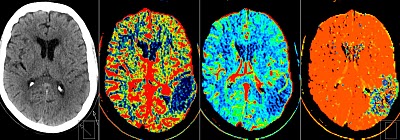

Figure 3 – CT Perfusion Study showing a Left Parietal Lobe Infarct:32

Essentially, CT Perfusion studies aim to identify areas of ischaemic brain tissue that may survive the acute phase of hypoperfusion if an adequate flow of cerebral blood is reestablished. As we discussed previously on page 4, this area of salvageable brain is known as the “ischaemic penumbra” and is readily identified by this CT technique.16

CT perfusion is performed by giving a bolus of radio-opaque contrast medium followed by the acquisition of multiple serial CT images which identify dynamic cerebral blood flow by looking at change over time.28 This imaging technique measures Cerebral Blood Volume (CBV) and the Mean Transit Time (MTT). By examining these two parameters radiologists can estimate Cerebral Blood Flow (CBF) using a standard algorithim.29

In general terms the ischaemic brain has a reduction in venous and arterial blood flow. This can be mapped radiologically by a CT perfusion study.5 The ‘Penumbra’ is identified as the area on the scan that has reduced Blood Flow (CBF) but a normal (or increased) Blood Volume (CBV). As a result, many perfusion studies show established infarcts and no area of brain that is salvageable, while other scans may show a ‘penumbra’ even after the established therapeutic time window of 4.5 hours.5

A recent Australian study by Campbell and colleagues suggested that CT perfusion studies increase the diagnostic accuracy during the initial acute care phase of stroke.33 This study, published in early 2013, suggested that CT perfusion:

- Was safe when used selectively (no reported cases of Acute Kidney Injury).

- Lead to an increased diagnostic yield compared to plain CT (80% v. 50%).

- The majority of scans were normal, which lead to the withholding of TPA.

- Was associated with improvements in technical adequacy over time.

- Took around 12 minutes to obtain images.